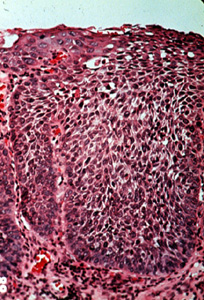

Con una resolución más alta de la

imagen 66, puede ser algo difícil determinar qué lado es la basal y

cual es la superficie. Las anormalidades celulares son obvias y la

maduración es casi inexistente. |

El fracaso de la queratinización del

epitelio, como en este

ejemplo típico de carcinoma in situ, significó que la enfermedad sería

muy difícil de descubrir clínicamente. Aunque algunos casos son

indudablemente invisibles, otros son rojos y ligeramente granulares o

aterciopelados debido a la inflamación y aumento de la vascularidad en el tejido

conjuntivo (como es visto aquí), o el carcinoma in situ alterna con

focos de displasia de la mucosa que producen queratina. Esto imparte una

apariencia roja y blanca manchada a la mucosa que es algo más fácil de

descubrir cuando se realiza un examen oral completo. |